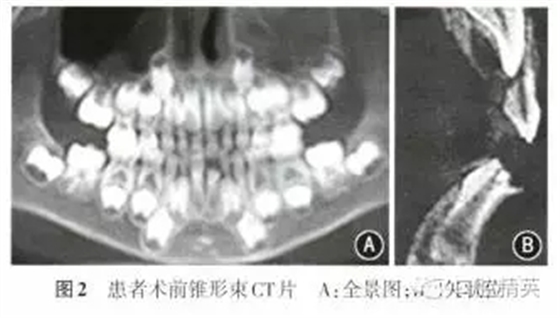

患者男性,7歲10個(gè)月,因左下乳前牙脫落后長(zhǎng)出一牙尖半年余要求治療,于2014年11月至南昌大學(xué)附屬口腔醫(yī)院口腔頜面外科門診就診?;颊呒韧w健,無牙病及外傷史,無家族史。體格檢查示身體發(fā)育正常,口腔檢查:II缺失,l缺牙區(qū)唇側(cè)可見一圓錐形牙尖突出于牙齦表面,色澤正常(圖1);66616已萌出,混合牙列,余未見明顯異常。錐形束CT檢查示1唇側(cè)鷹爪狀畸形尖,直徑約1.0 mm,長(zhǎng)度約3.2 mm,尖端離切緣約2.6 mm,不與髓腔相通;切緣形態(tài)亦發(fā)育異常,近髓角;牙根發(fā)育至根長(zhǎng)1/2左右,根尖呈喇叭狀;無先天性牙缺失及額外牙(圖2)。